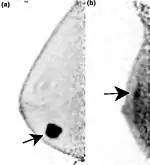

Two PEM images, including sites of tracer uptake | |